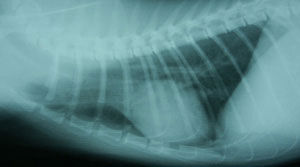

胸部X線検査所見:肺野にスリガラス状陰影、心陰影は不鮮鋭だが形状異常なし(図9)。

図9 症例3の胸部X線写真。肺野にスリガラス状陰影、心陰影は不鮮鋭だが形状異常はみられなかった。